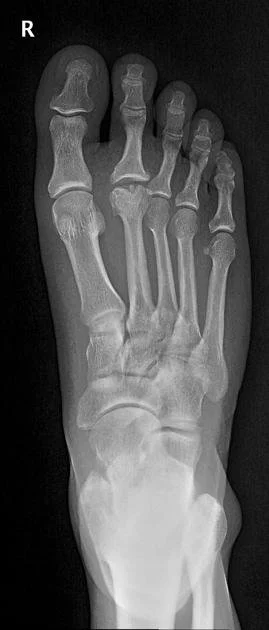

• Homolateral - basically all digits move laterally (1st digit may remain in place) (2nd picture)

• Case courtesy of Alexandra Stanislavsky, Radiopaedia.org, rID: 10919 (homolateral lisfranc injury)